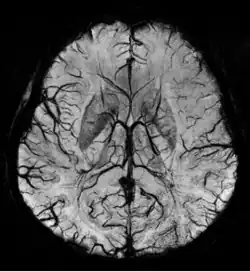

SWI Image acquired at 4 Tesla showing the veins in the brain.

Susceptibility weighted imaging (SWI), originally called BOLD venographic imaging, is an MRI sequence that is exquisitely sensitive to venous blood, hemorrhage and iron storage. SWI uses a fully flow compensated, long echo, gradient recalled echo (GRE) pulse sequence to acquire images. This method exploits the susceptibility differences between tissues and uses the phase image to detect these differences. The magnitude and phase data are combined to produce an enhanced contrast magnitude image. The imaging of venous blood with SWI is a blood-oxygen-level dependent (BOLD) technique which is why it was (and is sometimes still) referred to as BOLD venography. Due to its sensitivity to venous blood SWI is commonly used in traumatic brain injuries (TBI) and for high resolution brain venographies but has many other clinical applications. SWI is offered as a clinical package by Philips and Siemens but can be run on any manufacturer's machine at field strengths of 1.0 T, 1.5 T, 3.0 T and higher.